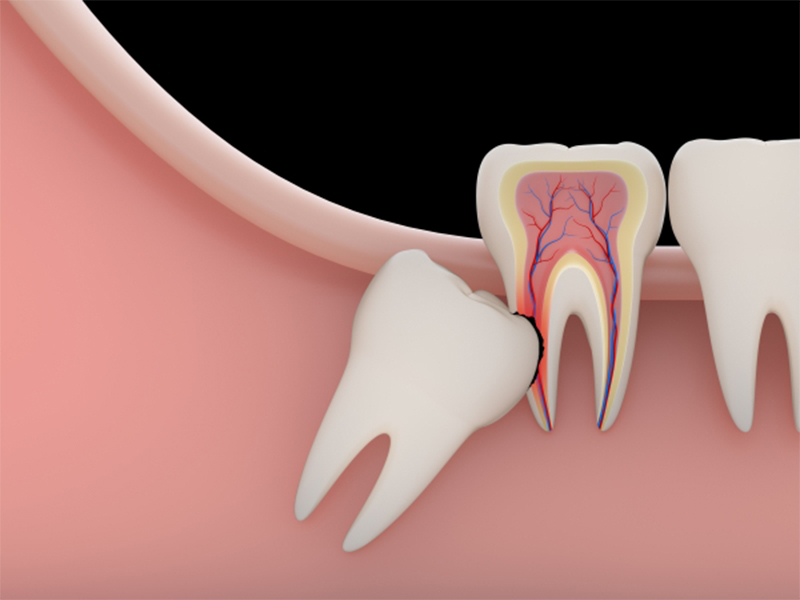

Răng khôn mọc lệch nếu không được điều trị kịp thời sẽ gây ra nhiều biến chứng nguy hiểm như:

Phần va chạm với răng kế cận sẽ khiến đau nhức toàn bộ vùng răng khôn phía trong, có thể khiến răng bên cạnh bị sâu răng, viêm tủy răng,…

Dẫn đến sự hình thành các u nang răng, thậm chí có thể gây hỏng răng số 7 nếu không nhổ răng khôn nằm ngang kịp thời.

Có thể gây xô lệch cả hàm răng nếu để tình trạng răng khô mọc lệch kéo dài quá lâu

Bị đau nhức âm ỉ kéo dài do răng khôn mọc lệch, sưng nướu, kèm áp xe, đau đầu, nóng sốt,…

Răng khôn (hay răng số 8) là chiếc răng mọc cuối cùng trên cung hàm, khi tất cả các răng khác đã mọc đầy đủ, xương hàm đã phát triển vững chắc và nướu cũng trở nên dày hơn. Do đó đôi khi việc này khiến răng khôn mọc khó khăn hơn sẽ gây ra tình trạng răng khôn mọc lệch.

Dưới đây là các kiểu răng khôn mọc lệch gây khó chịu, đau nhức cho người bệnh và cần được xử lý kịp thời để tránh các biến chứng nguy hiểm.